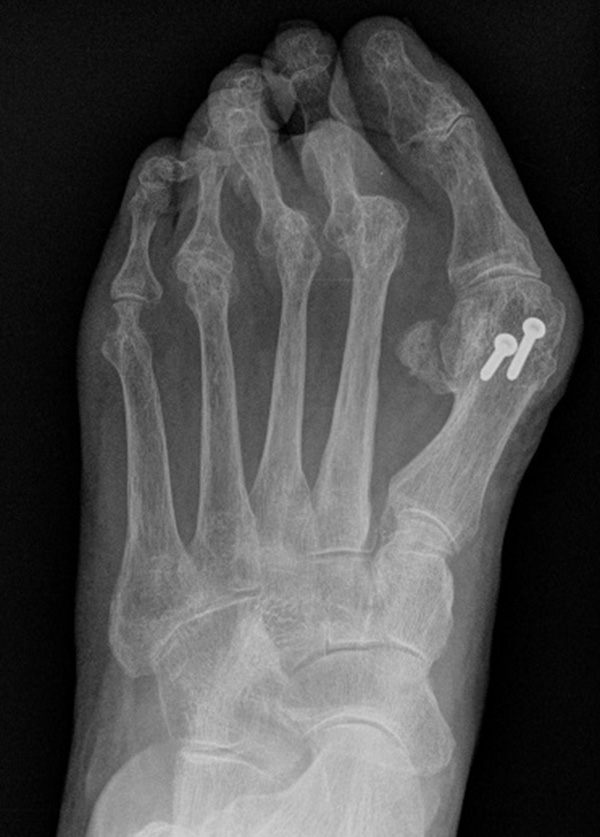

Nach Anamnese und Untersuchung reichen meist konventionelle Röntgenbilder mit Belastung im Stehen a.p. und seitlich ggf. Schrägaufnahmen zur Beurteilung und Indikationsstellung aus. CT oder MRT sind in der Regel nicht erforderlich, im Einzelfall aber ergänzend sinnvoll. Szintigraphie und Sonographie spielen bei der Indikationsstellung und Operationsplanung eine untergeordnete Rolle.

Zum Lesen der Bildbeschreibung und zur Vollansicht bitte die Bilder anklicken.